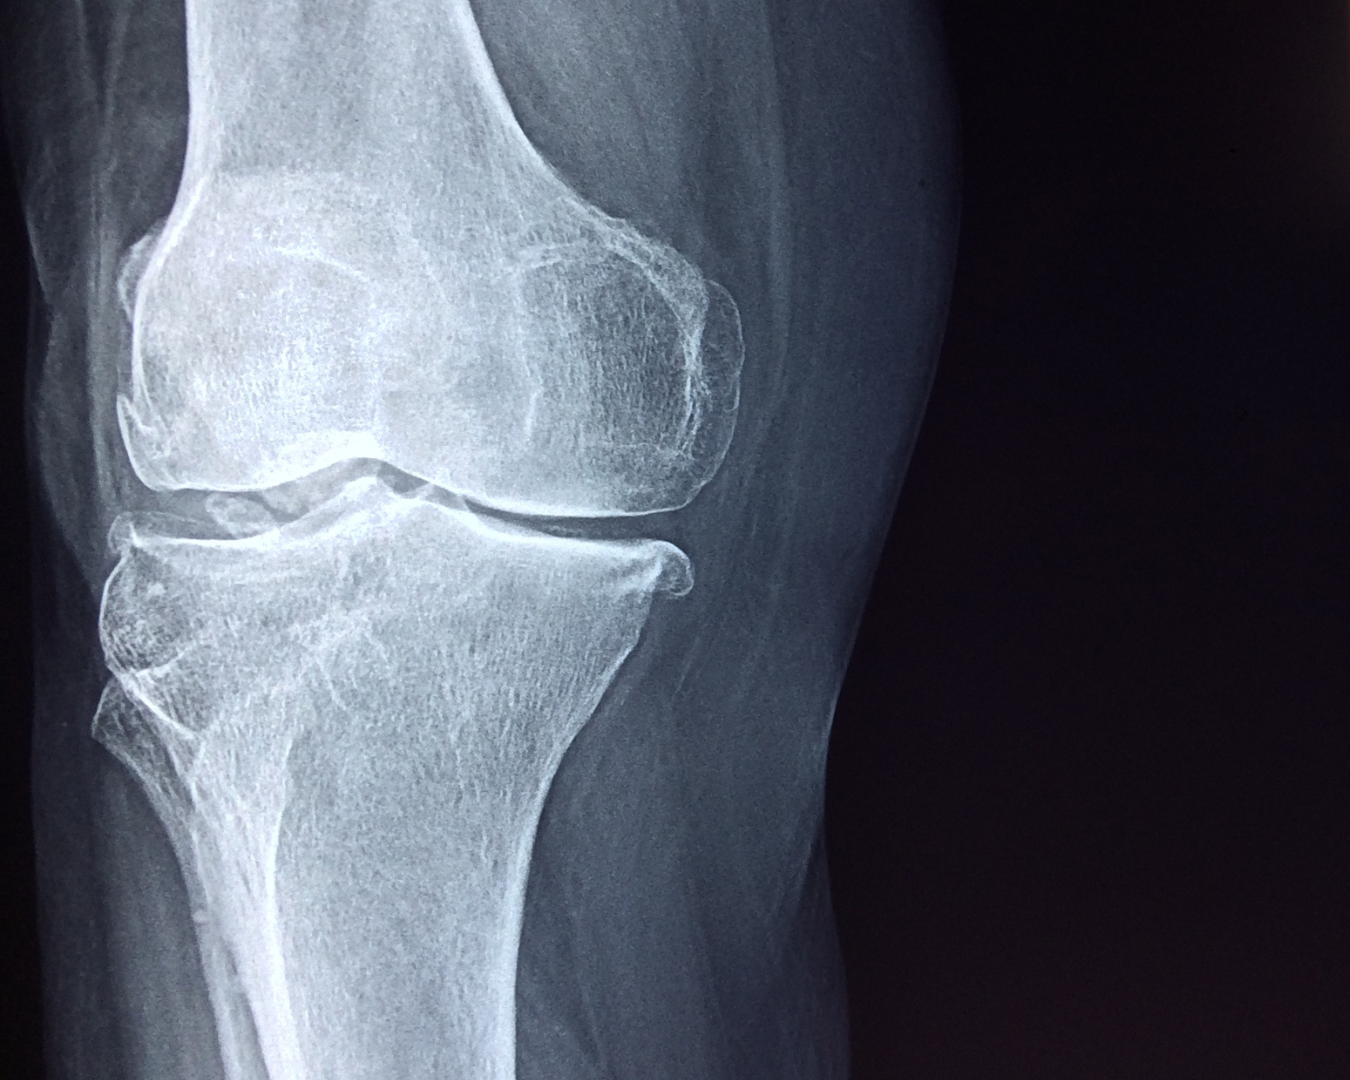

A artrose ou osteoartrose é uma doença articular degenerativa que pode afetar qualquer articulação do corpo, mas está associada com articulações que suportam peso como o quadril. Com o passar do tempo, devido ao envelhecimento, trauma ou outros fatores, a cartilagem que reveste as articulações começa a se deteriorar. Sem cartilagem, as articulações perdem sua função e os ossos começam a se raspar diretamente à medida que a pessoa se movimenta.